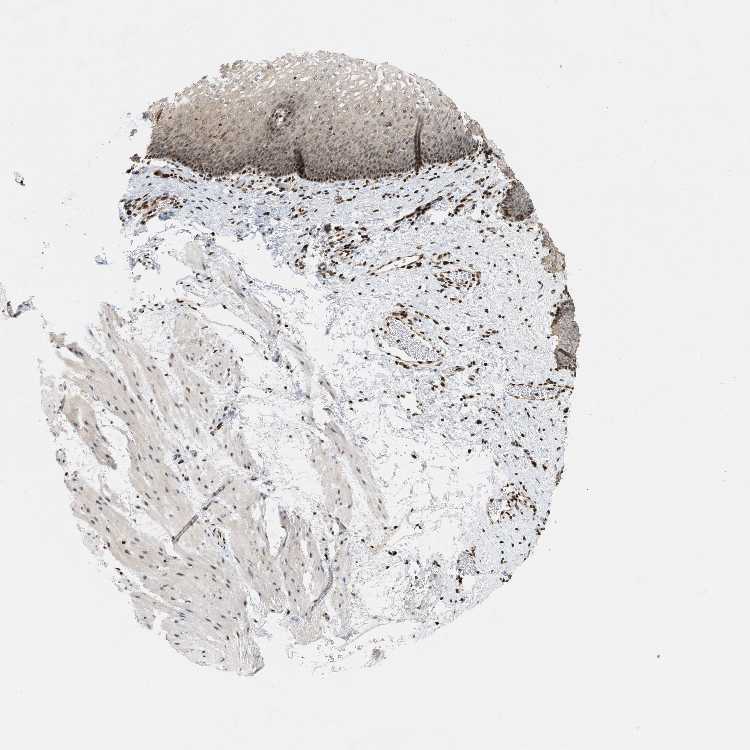

ESOPHAGUS - Antibody stainingi

Antibody staining in the annotated cell types in the current human tissue is reported as not detected, low, medium, or high, based on conventional immunohistochemistry profiling in selected tissues. This score is based on the combination of the staining intensity and fraction of stained cells.

Each image is clickable and will lead to virtual microscopy that enables deeper exploration of all samples and also displays staining intensity scores, fraction scores and subcellular localization as well as patient and tissue information for each sample.

Antibody HPA016736

Squamous epithelial cells Medium